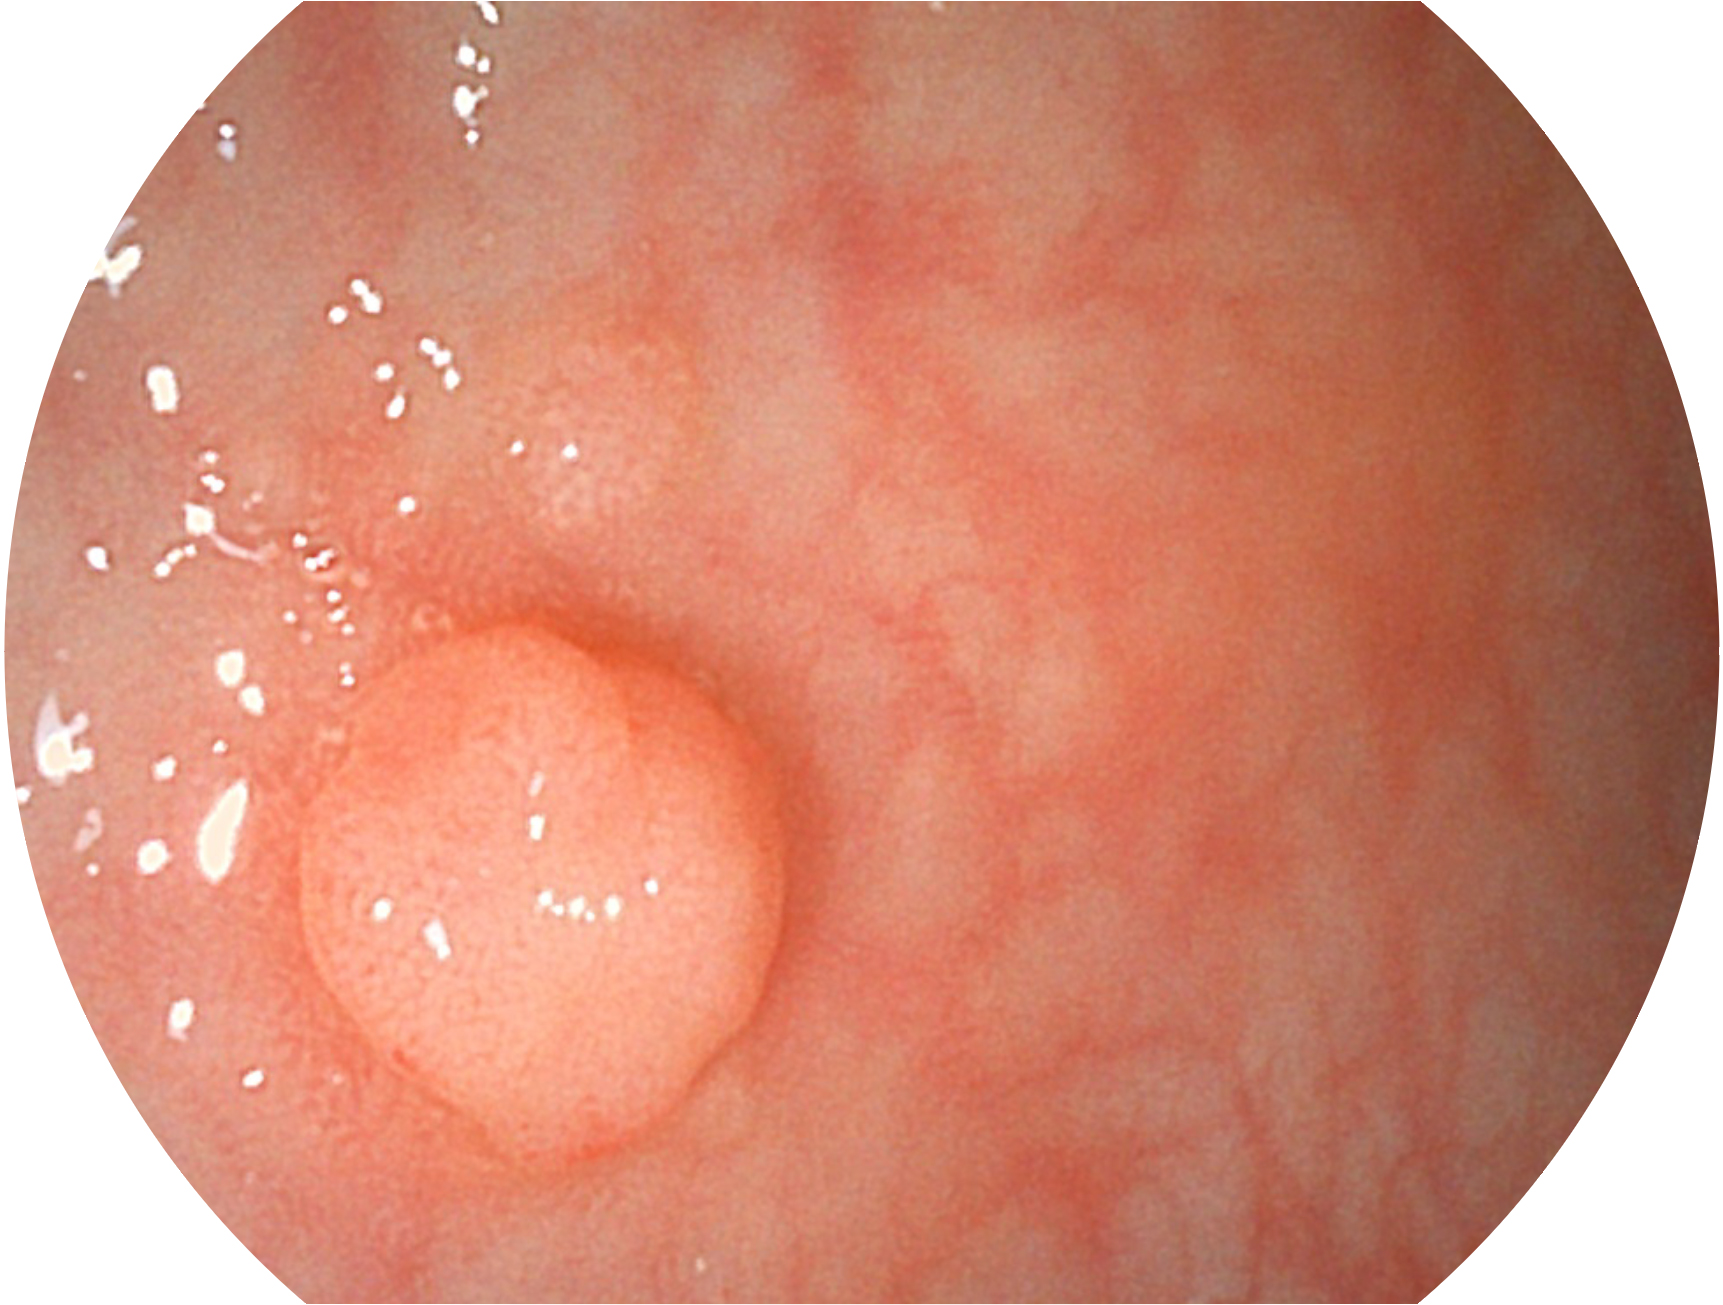

美狮贵宾会官网新开发的内镜染色技术,主要是基于多波长LED 光源的开发,VLS-55Q 四波长LED 光源是由四个不同颜色的LED光按照相应照明模式所规定的特定发光比例进行合束后形成,合束后形成的照明光的光谱由红光、绿光、蓝光及蓝紫光这四个不同的波段范围构成。具有更高光谱自由度,通过光谱比例的控制,实现了聚谱成像技术,英文全称为“Spectral Focused Imaging, SFI”,缩写为“SFI”和光电复合染色成像技术,英文全称为“Versatile Intelligent Staining Technology, VIST”,缩写为“VIST”。